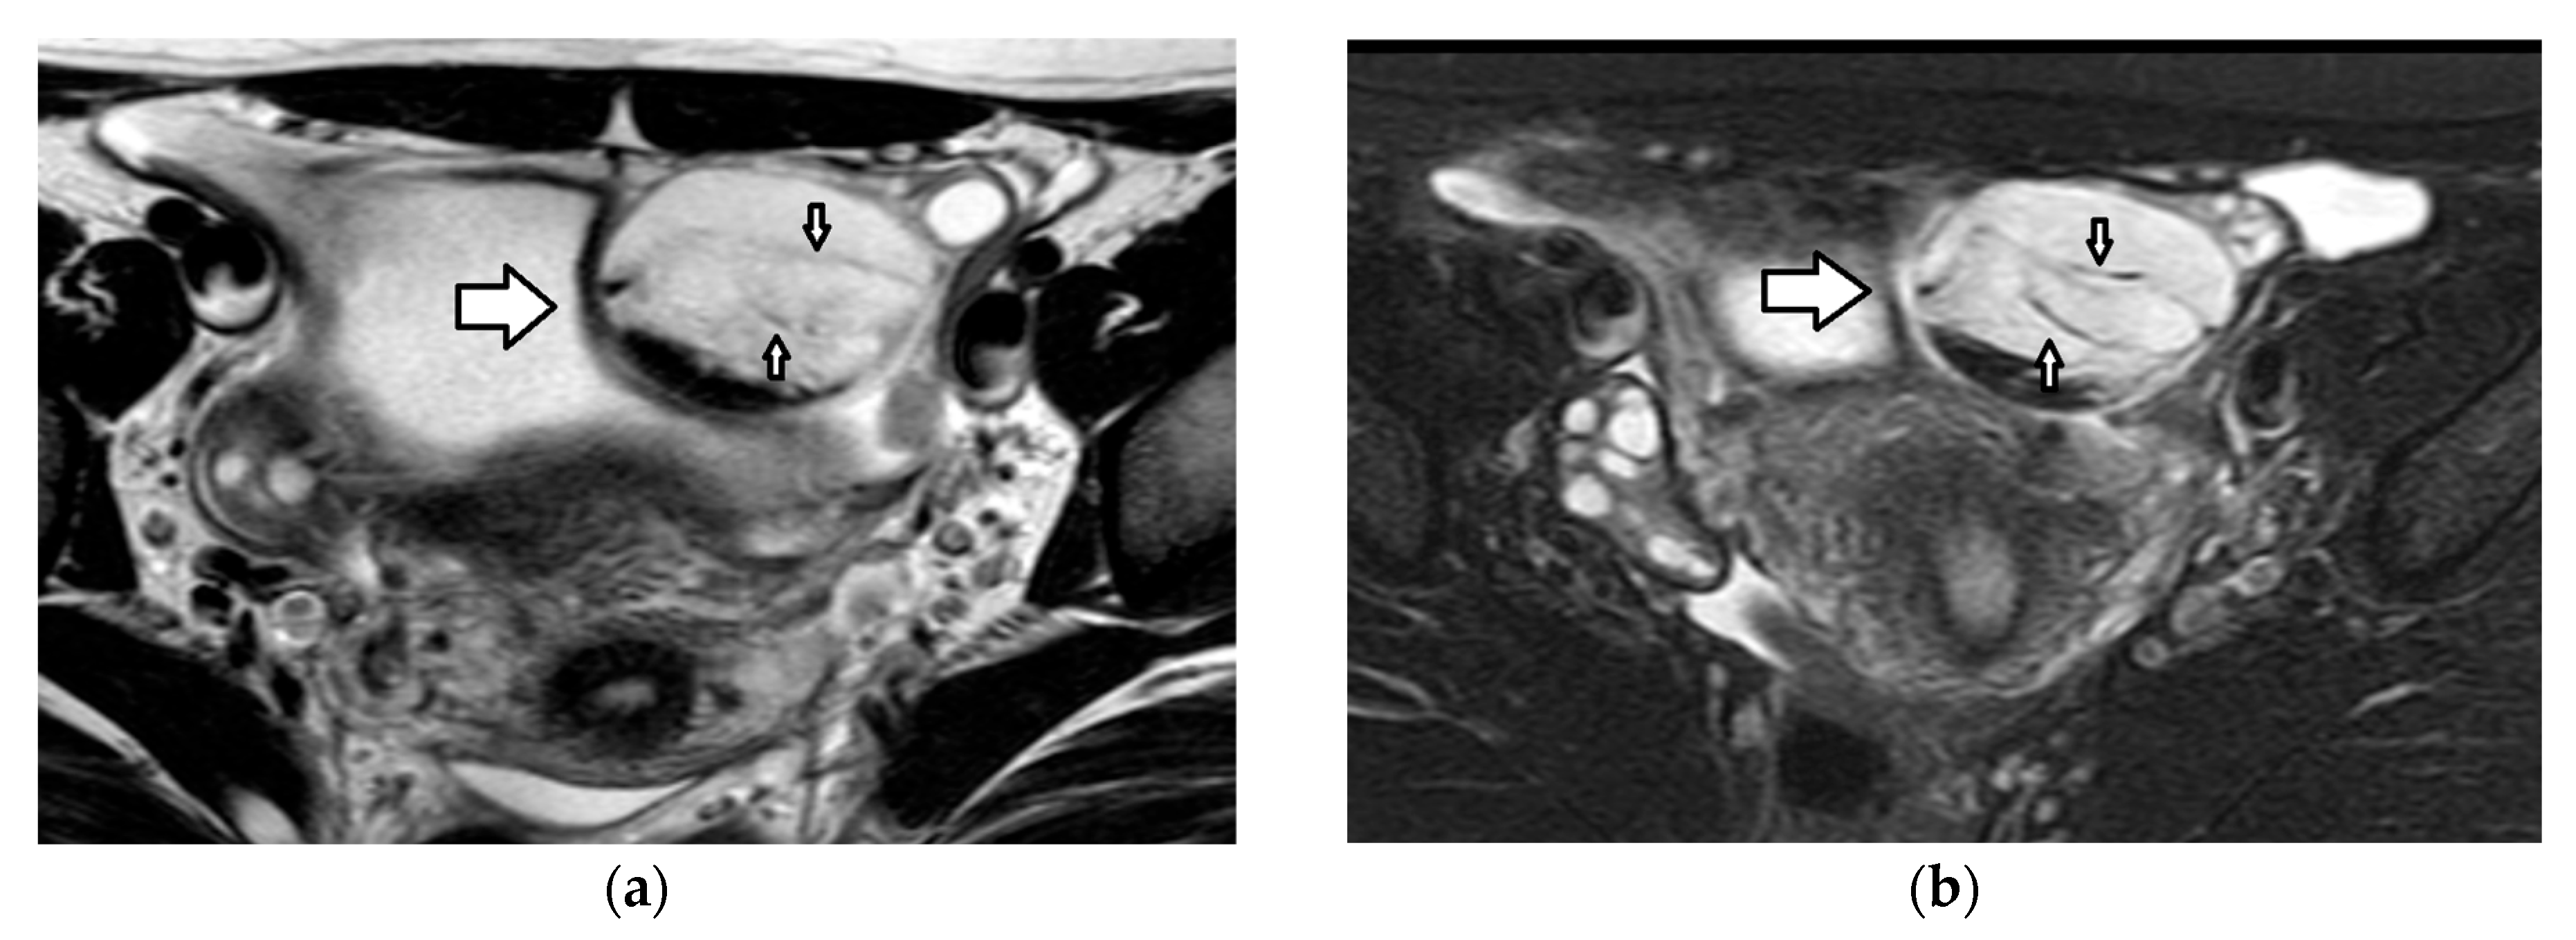

3.3. Ovarian Torsion